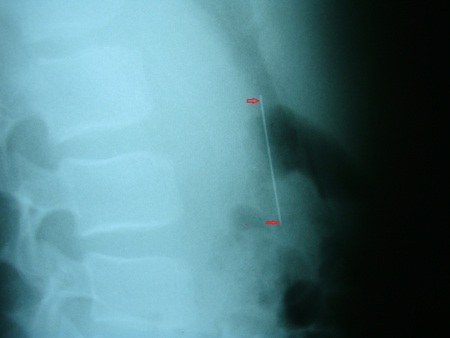

Ngay lập tức, Phước được đưa đi chụp X Quang và kết quả cho thấy chiếc kim may dài 6cm hiện đang nằm dọc trong dạ dày bệnh nhân này.

Theo các bác sĩ bệnh viện, thì đây là một tai nạn hy hữu, nếu dị vật ngắn và tù thì có thể được thải qua đường tiêu hóa. Nhưng do đây là một vật sắc nhọn, dài nên diễn biến rất khó lường và có thể có nhiều biến chứng.

Hiện cháu Phước đang được theo dõi thông qua các phương tiện y tế để biết đường đi của chiếc kim và có hướng điều trị kịp thời.